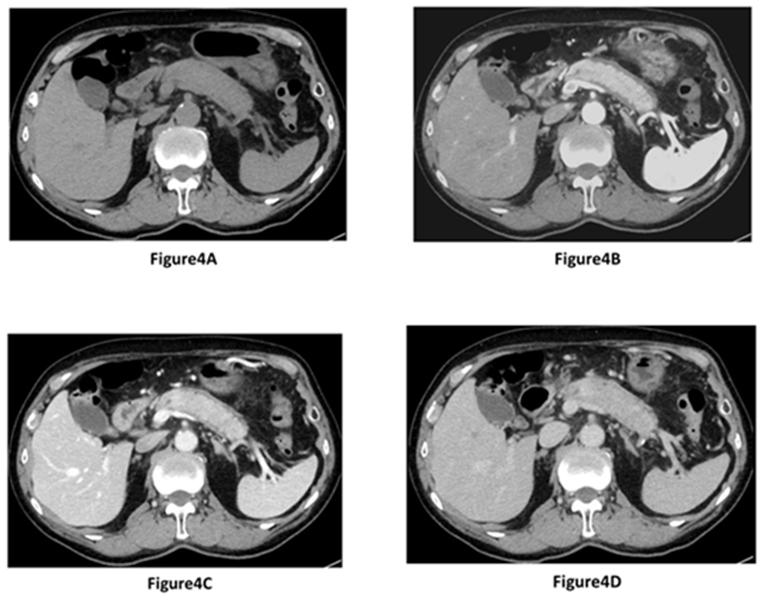

Quadriphasic CT, performed 24 months after the initial hospitalization, revealed segmental enlargement of the pancreas body and tail with a capsule-like low density rim. Segmental enlargement of the pancreatic parenchyma appeared hypoattenuating compare to normal spleen parenchyma during the pancreatic phase of the dynamic study (Figure 4B). This pancreatic parenchyma became more dense during successive phases of study, and appeared isoattenuating compare to normal spleen parenchyma during portal venous (Figure 4C) and delayed (Figure 4D) phases. Moreover, on MRCP, progression of MPD narrowing was noted (Figure 1D). At that time, the serum IgG4 level was elevated to 163 mg/dL. The serum levels of CEA and CA19-9 were 3.8 U/mL and 13.6 U/ mL, respectively. EUS revealed a segmental enlargement and a capsule-like rim in the pancreas body and tail. In addition, segmental narrowing of MPD was observed on ERP (Figure 2B). Thus, the patient was diagnosed with diffuse type AIP according to the JPS2011 [2] and ICDC [3]. EUS-FNA of the pancreatic body was performed to obtain histopathological evidence of AIP. The obtained tissue showed no malignancy, but lymphoplasmacytic infiltration, storiform fibrosis, obliterative phlebitis, and abundant IgG4-positive plasma cells were not observed. Therefore, it did not meet the histological criteria of JPS2011 and ICDC. In the present case, we did not administer steroid therapy because the patient had no symptoms and was of advanced age. The patient was discharged and followed- up for 6 months after the diagnosis of AIP.

Figure 4A-D. Dynamic study of contrast-enhanced CT after 24 months; A. Segmental enlargement of the pancreas body and tail during precontrast phase; B. Segmental enlargement of the pancreatic parenchyma appears hypoattenuating during the pancreatic phase compare to normal spleen parenchyma, with a capsule-like low density rim; C. Pancreatic parenchyma appears isoattenuating during the portal venous phase compare to normal spleen parenchyma; D. Pancreatic parenchyma appears isoattenuating during the delayed phase compare to normal spleen parenchyma. |

We consider that CT finding after 15 months follow-up was crucial because this could be the initial focal lesion of AIP in the present report. In the present study, the focal lesion appeared hypoattenuating during the pancreatic phase, and isoattenuating compare to normal adjacent pancreatic parenchyma during both portal venous and delayed phases. Typical dynamic CT findings of AIP reveal hypoattenuating during the pancreatic phase, and hyperattenuating in both portal venous and delayed phases [8]. CT finding during the portal venous phase is useful in differentiating focal AIP from pancreatic adenocarcinoma. Focal AIP during the portal venous phase appear hyperattenuating at diagnosis, and this finding is different from the findings of pancreatic cancer which most frequently remains hypoattenuating during the portal venous phase. The present case did not appear hypoattenuating during the portal venous phase, and this CT finding did not suggest pancreatic cancer.

In the present study, the evolution of focal to segmental change was observed. Focal AIP after 15 months and segmental AIP after 24 months showed similar CT finding in each different phase (pancreatic, venous, and delayed phases). Therefore, we predict that histpathological might be similar between focal and segmental AIP. On the other hand, Sahani et al. [9] reported that diffuse swelling reflects an early inflammatory phase and focal masslike swelling symbolize a late stage with predominance of fibrosis because focal mass like swellings persisted after resolution of diffuse changes in 7 of 13 patients. Further studies should be conducted to clarify the clinical and histopathological differences between focal and diffuse AIP.